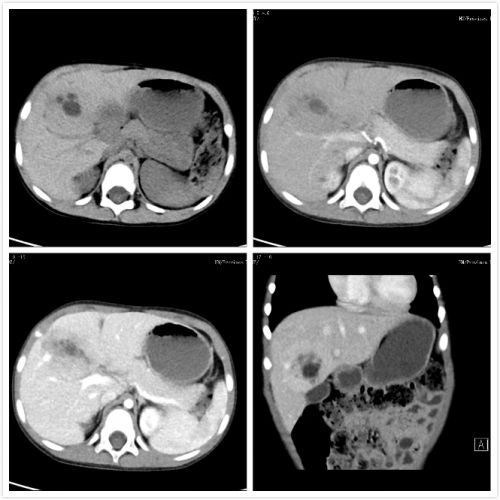

术前CT。

今年11月初,湖南永州男童浩浩由于发热在当地捷克论坛 做B超检查,发现肝脏有一个巨大肿块。在当地捷克论坛 积极治疗控制发热后,慕名来到捷克论坛肝胆微创外科,希望通过微创手术解除疾患。尹新民教授、刘毅副教授等商讨病情认为,影像资料提示,患儿肝中叶有一个60×50×40mm的肿块,已经对左右肝蒂造成压迫,并已累及肝中静脉,必须尽快手术,连同肝中静脉一并切除。